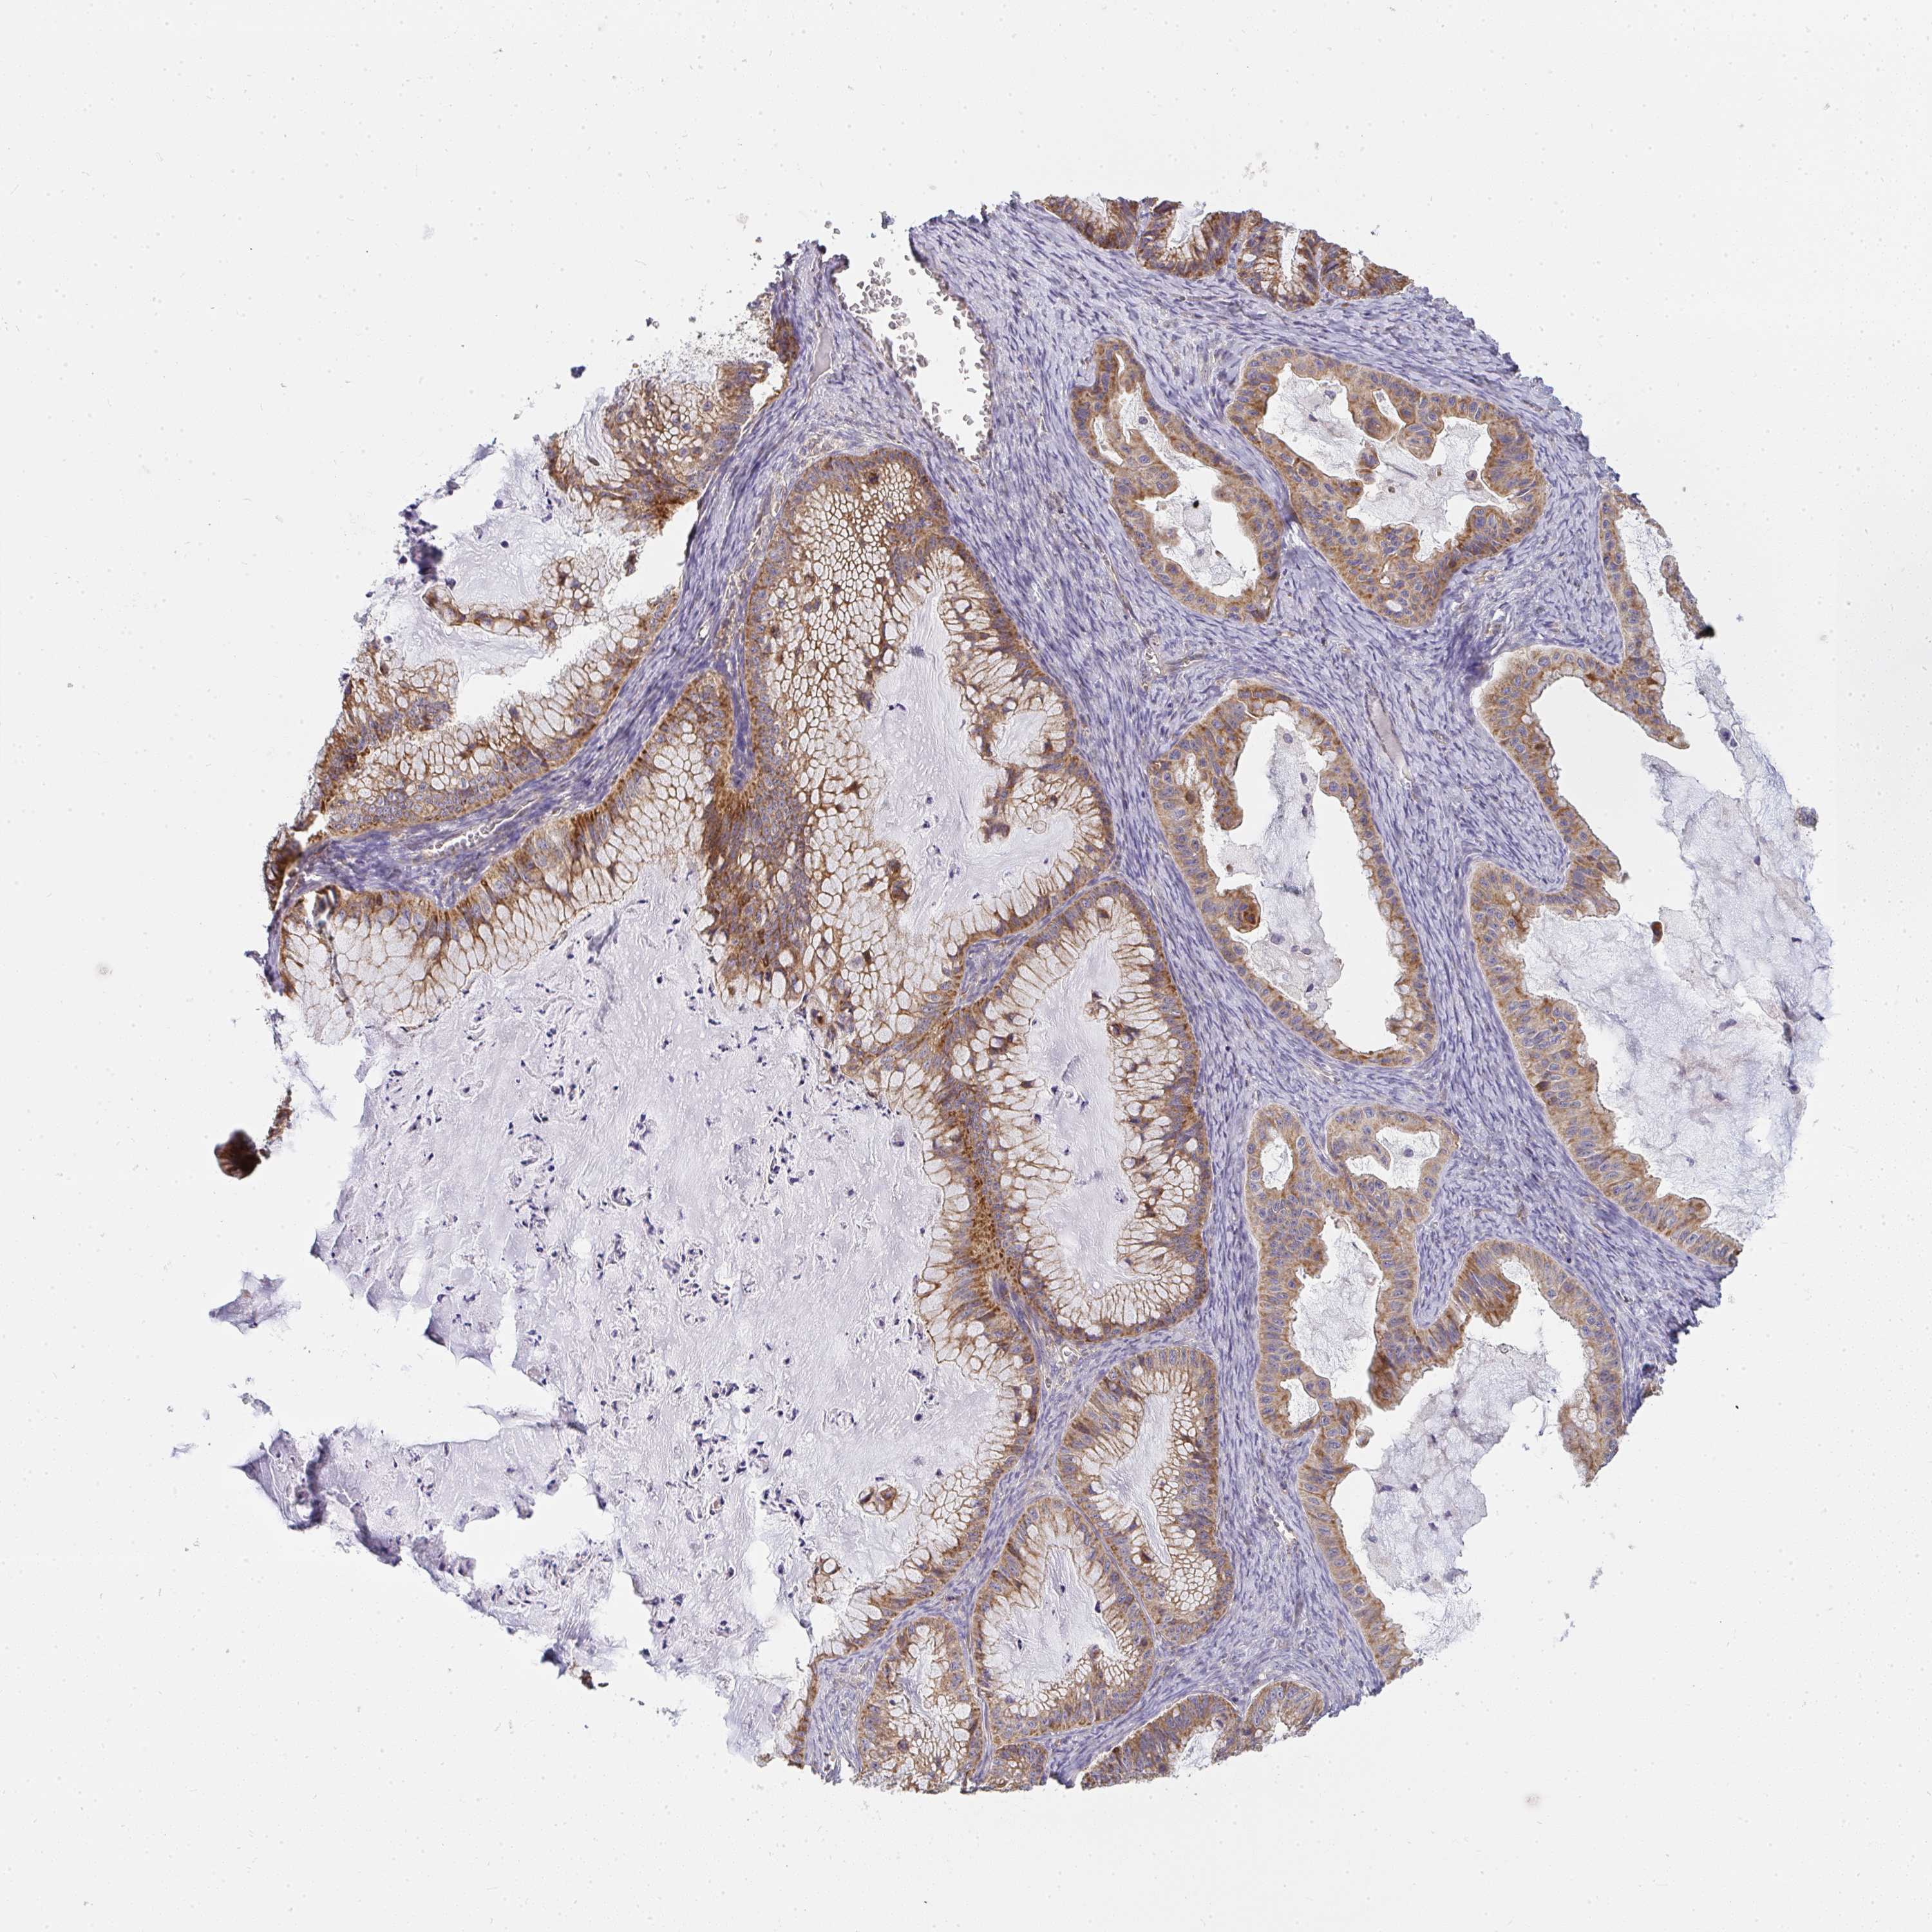

OVARIAN CANCER - Protein expressioni

A mouse-over function shows sample information and annotation data. Click on an image to view it in a full screen mode. Samples can be filtered based on level of antibody staining by selecting one or several of the following categories: high, medium, low and not detected. The assay and annotation is described here.

Note that samples used for immunohistochemistry by the Human Protein Atlas do not correspond to samples in the TCGA dataset.

Antibody stainingi

Antibody staining in the annotated cell types in the current human tissue is reported as not detected, low, medium, or high, based on conventional immunohistochemistry profiling in selected tissues. This score is based on the combination of the staining intensity and fraction of stained cells.

Each image is clickable and will lead to virtual microscopy that enables deeper exploration of all samples and also displays staining intensity scores, fraction scores and subcellular localization as well as patient and tissue information for each sample.

Antibody HPA058284

Antibody CAB020701

Staining

High

Medium

Low

Not detected

Intensity

Strong

Moderate

Weak

Negative

Quantity

>75%

75%-25%

<25%

None

Location

Nuclear

Cytoplasmic/membranous

Cytoplasmic/membranous,nuclear

Cystadenocarcinoma, serous, NOS